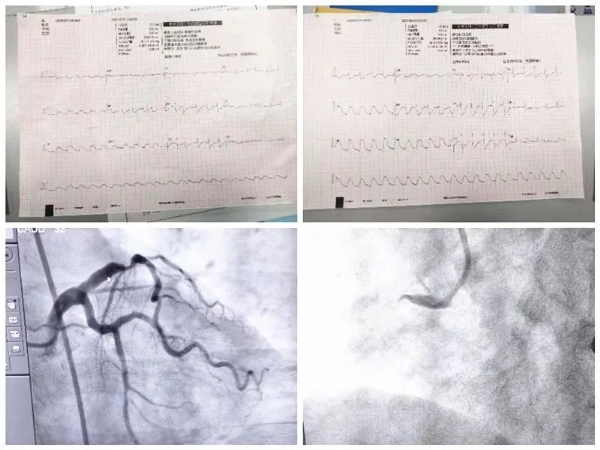

近日,患者杜某,女,59岁,到我院心血管病科就诊。心血管病科副主任梁鸿雁识别患者为高危患者,随时会有生命危险,立即通知心电图室工作人员到心血管病科诊室行心电图检查。患者在等待过程中,突然出现心脏骤停,梁鸿雁立即将患者搬至检查床进行心肺复苏,并同时联系急诊科及心血管病科主任阚国庆进行紧急会诊。阚国庆主任联系麻醉科主任郑均旗安排麻醉医师至心血管病科门诊待命。急诊人员迅速到位,并迅速投入到抢救工作,抢救过程中患者多次出现室速及室颤,其间行电除颤多次,待患者病情相对稳定后,紧急转运患者至ICU进行下一步抢救工作,同时通知急诊PCI团队立即到位等待行急诊PCI手术。

在整个抢救过程中,所有医护人员各司其职,抢救工作高效、有序进行,通过电除颤等一系列的抢救措施,患者生命体征相对稳定。阚国庆主任与患者家属沟通病情,结合患者疾病特点,应立即行急诊冠脉造影及急诊冠状动脉支架植入术,否则患者随时存在生命危险,患者家属表示知情并理解,同意进行手术治疗。遂将患者立即平稳转运至导管室行术前准备,同时麻醉科团队也迅速到位做好手术保障工作。造影示:前降支中段70%—80%狭窄,右冠开口100%闭塞,立即开通闭塞的右冠,给予充分缺血预适应,患者血管开通后,多次出现室性心动过速、室颤,先后给予11次电除颤,并根据心率、血压及时调整药物,待患者心率、血压稳定后,于右冠近段置入支架1枚。由于患者心肌梗死面积大,为了更好地避免心力衰竭及其他器官灌注不足,术后立即置入主动脉球囊反搏泵(IABP)以减轻心脏负荷、保证重要脏器血液灌注。北京中医药大学东方医院驻我院专家范宗静主任给予患者床旁心脏彩超检查评估病情并指导治疗,经过治疗患者安全转出ICU到心血管病房继续治疗,在病房患者感谢阚国庆主任紧紧握住他的手不能松开,还给阚主任点赞,这一握手是患者对我们的感谢、对医护人员工作的肯定,也是我们一直奋斗的动力源泉。